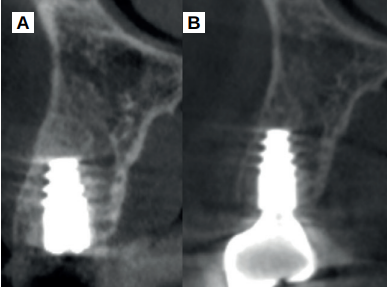

En la Historia Clínica no se evidenciaron antecedentes médico-quirúrgicos de interés, alergias medicamentosas conocidas ni hábitos nocivos. En la exploración intraoral, se apreció un implante en la localización del 1.6, con un pilar de cicatrización, y el diente 1.5 con un ferrule insuficiente para ser restaurado (Figura 1). En la exploración radiográfica, mediante escáner de haz cónico (CBCT), se apreció un tratamiento de conductos en el 1.5, así como una imagen radiolúcida a nivel apical (Figura 2). Se planificó la exodoncia del 1.5, para lo que se firmó previamente el consentimiento informado. Tras el mismo, se realizó un bloqueo anestésico mediante articaína al 4% con adrenalina 1:100.000 del nervio alveolar superior posterior y medio y el nervio palatino anterior. Se realizó la extracción de la forma más atraumática posible y se eliminaron del diente el cálculo y los restos de obturaciones con fresa de diamante de turbina (Dentsply Maillefer, Ballaigues, Suiza). Se pulió la superficie radicular con fresas de diamante de turbina con abundante irrigación, eliminando de esta forma el ligamento periodontal. El material de relleno endodóntico fue retirado usando fresas de Gates Glidden® (Dentsply Sirona Inc, Delaware, Estados Unidos) (Figura 3). Se cortó el diente en fragmentos ≤ 5 mm y se colocaron secos dentro del molino del dispositivo Tooth Transformer® (S.R.L, Milan, Italia) como indica el fabricante.

A los 15 días se retiraron los puntos de sutura, apreciándose un buen aspecto de los tejidos blandos y la presencia de fibrina sellando la herida (Figura 7). Tras tres meses de cicatrización se comprobó su evolución mediante CBCT, apreciándose el mantenimiento de las dimensiones óseas en comparación con el escáner realizado antes de la extracción (Figura 8).

Cinco meses tras la colocación del implante, se realizó la toma de impresiones para la realización de una corona cemento-atornillada sobre una base de titanio. Un año tras la colocación de la corona, se observó el buen aspecto gingival (Figura 14) y radiográfico, donde se observa una pérdida ósea marginal fisiológica en las radiografías periapicales (Figura 15), y en los cortes del CBCT (Figura 16).

B. Corte sagital al año de la carga prostodóncica.